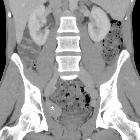

Post-thrombotic

aneurysmal dilatation of the hypogastric vein. The venous phase acquisition (d-h) showed the lesion (*) to enhance homogeneously and synchronously with venous vessels, consistent with aneurysmal dilatation of the proximal hypogastric vein. Urinary bladder (+).

aneurysmal dilatation of the hypogastric vein. Coronal (f) and sagittal (g,h) reconstructions confirmed aneurysmal dilatation (*) of the right hypogastric vein without signs of thrombosis. No abnormal dilatation, compression or thrombosis of the inferior cava, common and external iliac veins.